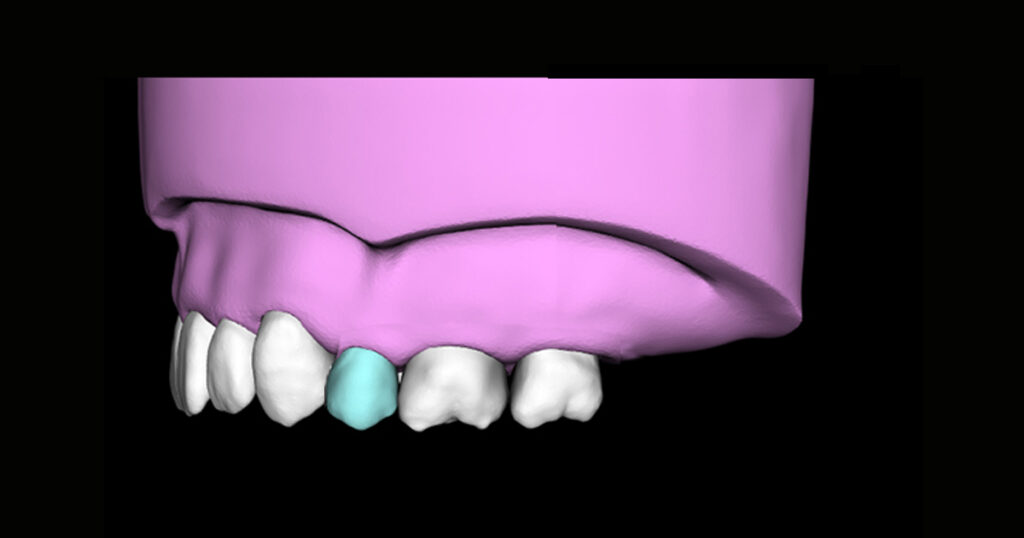

• 歯周病治療と部分矯正後に口腔内スキャンを利用し中切歯の修復

歯周病で歯並びが崩れた前歯を歯周治療と部分矯正後に矯正装置を付けたまま、口腔内スキャナーを使ったデジタル印象にてジルコニアセラミック冠を製作。 同時に3Dプリンター(ステレオリソグラフィー)にて得られた模型を調整して、マウスピースタイプ...